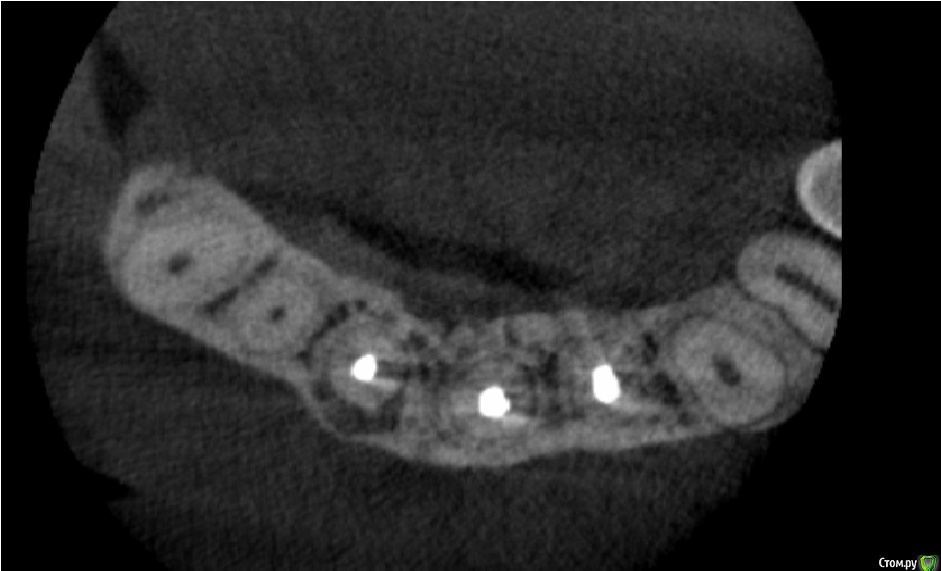

Doctor Vlad Опубликовано 29 августа, 2016 Поделиться Опубликовано 29 августа, 2016 Добрый день, уважаемые доктора!Оцените возможность сохранения 11 зуба с маргинальной и апикальной резорбцией зуба. причину на кт не нашел, но корень тоже поеден. переломов не определил. пломбирован гомогенно! мб перегрузка штифта? зубы 21 и 22 ранее ( 2 года назад по словам) сделана рвк; есть смысл повторной операции? Ссылка на комментарий

Doctor Vlad Опубликовано 30 августа, 2016 Автор Поделиться Опубликовано 30 августа, 2016 Может перегрели если бифилом пломбировали. Как вариант. Вроде с чего бы здесь трещина.если и грели то по словам более 2 лет назад, сейчас то что делать)? там весь фронт разочарование сплошное. 21 и 22 зубы рецедив после рвк тоже 2 года назад на фоне гомогенно обтурированных каналов... а я лишь для себя понять хочу че с этим сделать можно? 1 1 Ссылка на комментарий

Doctor Vlad Опубликовано 31 августа, 2016 Автор Поделиться Опубликовано 31 августа, 2016 В области 11 очаг не большой можно и одномоментно. А вот в 21 22 после резекции очаг до 8мм там решить нужно. Ссылка на комментарий